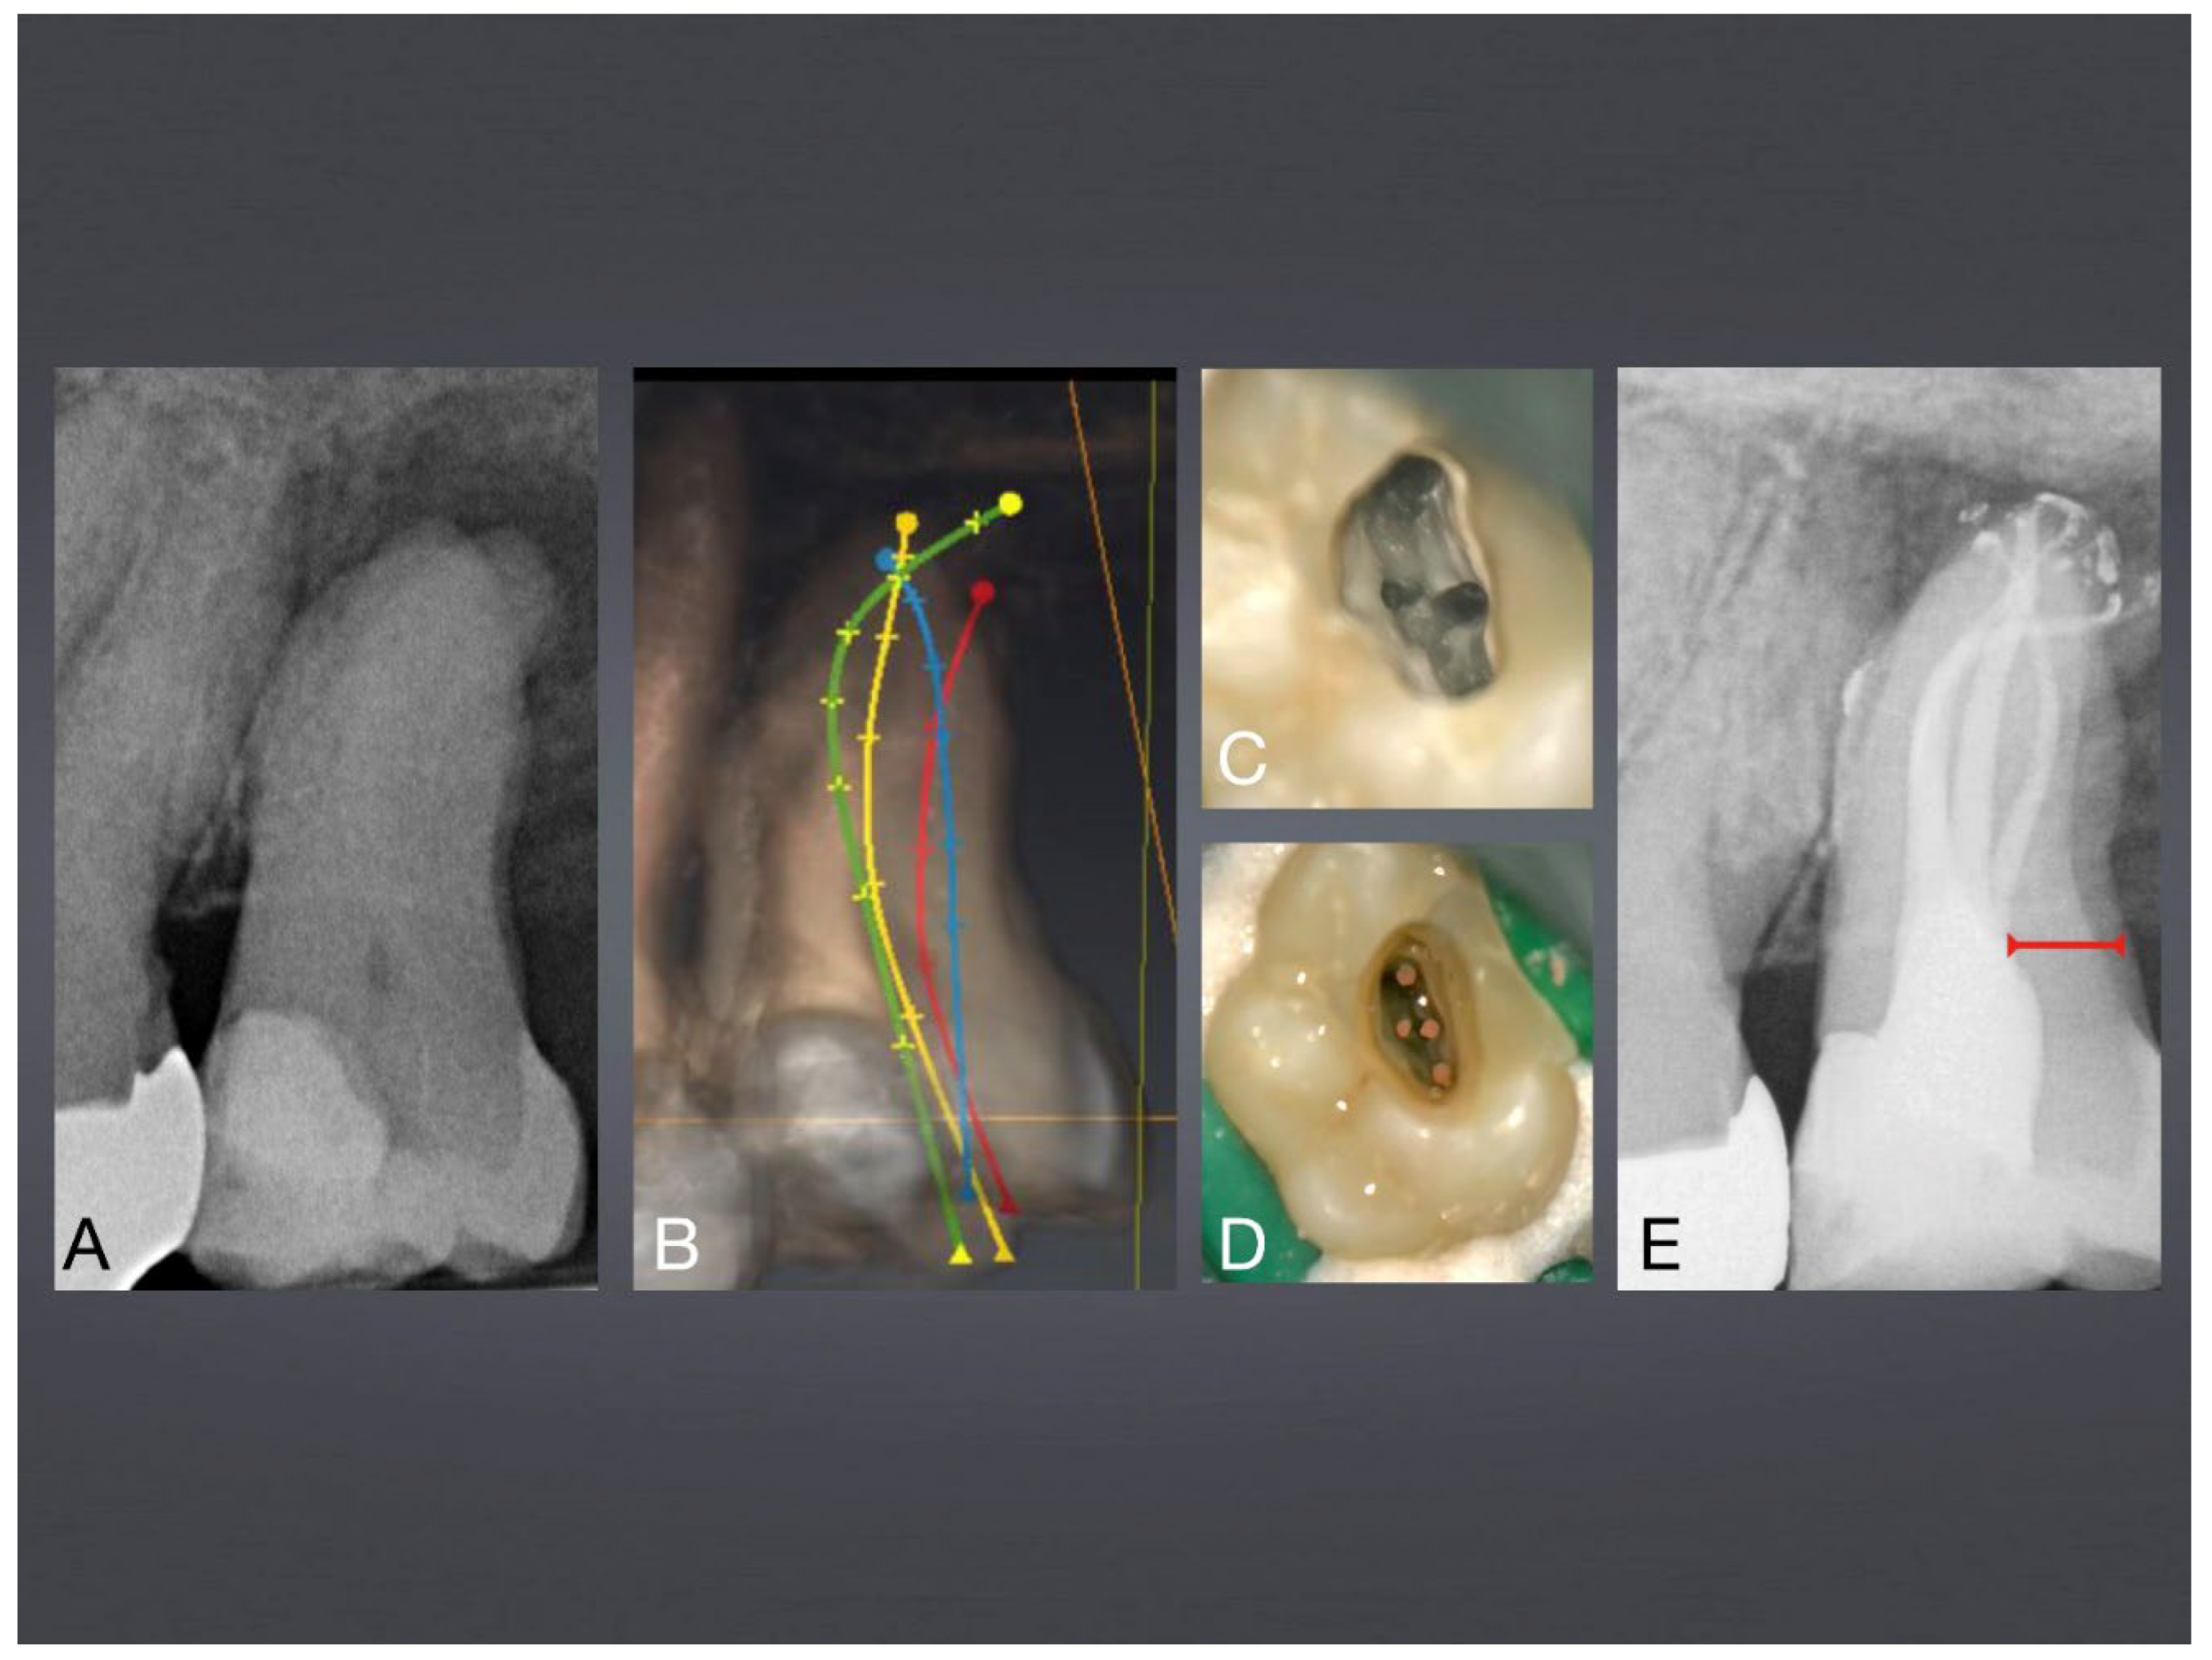

Figure 6. Mandibular premolar with 3 S-shaped roots with 20° root canal access access angle. A: final X-ray after root canal treatment via occlusal surface, see preserved peri-cervical dentin (red line), characterizing microinvasive endodontics. B: Access cavity planning with SICAT-Endo guiding software. C: Occlusal access via preexisting crown restoration.